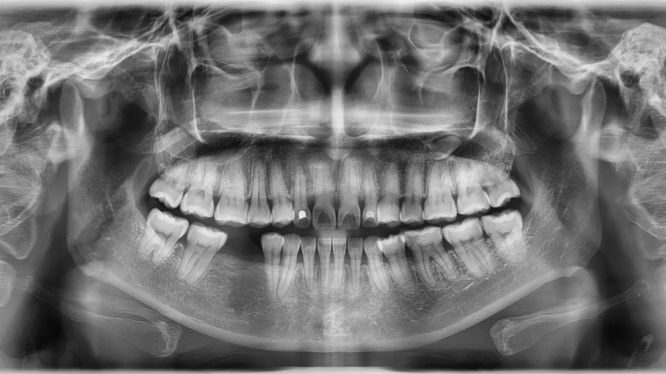

En odontología, la radiografía panorámica es uno de los estudios más solicitados por dentistas y ortodoncistas, y no es casualidad. Este estudio no invasivo permite observar en una sola imagen toda la estructura ósea de la boca, desde la mandíbula hasta el maxilar superior, incluyendo dientes, senos paranasales, articulaciones y más.

La radiografía panorámica (también conocida como ortopantomografía) es un estudio de imagen extraoral que permite visualizar en una sola toma toda la estructura ósea de la boca y el rostro inferior, incluyendo:

- Mandíbula y maxilar

- Dientes superiores e inferiores

- Articulaciones temporomandibulares (ATM)

- Senos maxilares

- Huesos faciales

- Raíces dentales

- Muelas del juicio (aunque aún no hayan salido)

- Dientes impactados o no erupcionados

A diferencia de otras radiografías dentales más focalizadas (como las periapicales o bitewing), la panorámica ofrece una vista completa, lo que la convierte en una herramienta indispensable para la evaluación global del paciente.